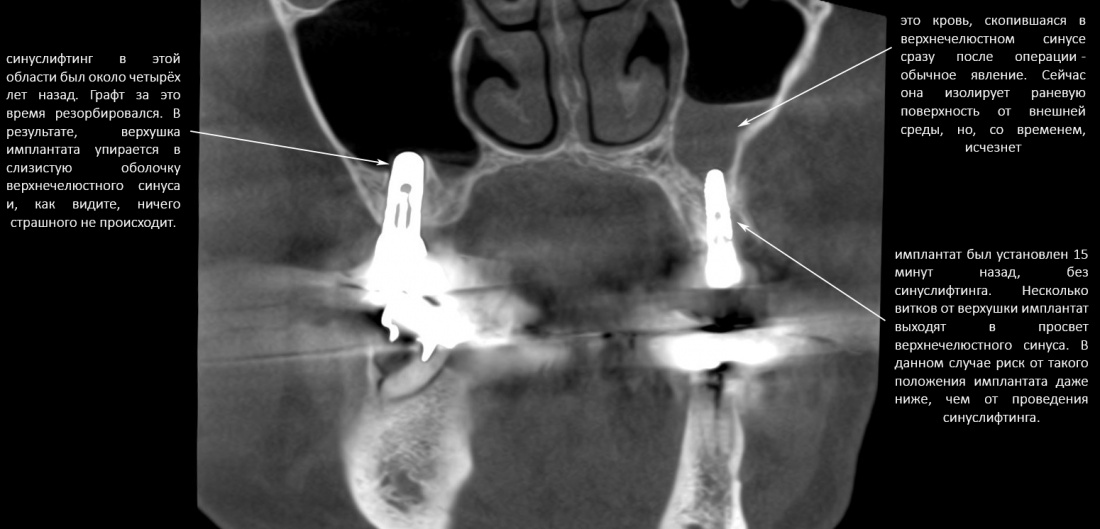

Это, кстати, значит, что в пограничных случаях (например, при расстоянии АБ=8 мм и длине имплантата 9 мм) мы можем вполне себе обойтись без синуслифтинга, поскольку попадание верхушки имплантата в просвет верхнечелюстного синуса на 1-1,5 мм не несёт в себе каких-либо рисков. Более того, если мы с вами сделаем и изучим КЛКТ пациентов с имплантатами и т . н. «закрытым» синуслифтингом, проведенным 5-6 лет назад, то увидим, что в половине случаев верхушки имплантов так или иначе выходят в просвет гайморовой пазухи:

Другими словами, не парьтесь. Риск от операции синуслифтинга, даже закрытого, выше, чем вероятность осложнений от попадания двух витков имплантата в просвет верхнечелюстной полости. Не усложняйте жизнь себе и вашим пациентам — если расстояние до дна пазухи меньше желаемой длины имплантата на 1 мм — просто ставьте имплантат. И все будут счастливы.